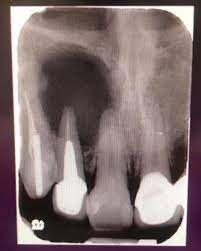

Fractura Radicular Vertical

Una fractura radicular vertical es una fisura que se extiende a lo largo de la raíz del diente, a menudo causada por un trauma o una presión excesiva.

Los pacientes suelen sentir dolor al morder y pueden notar hinchazón.

La fractura generalmente requiere la extracción del diente, ya que es difícil de reparar. Es crucial tratarla rápidamente para evitar infecciones.